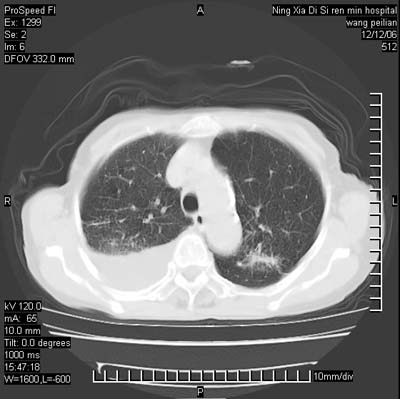

标题: CT5609:胸部:女77 病史不详 [打印本页]

标题: CT5609:胸部:女77 病史不详

两肺可见多个大小不等的结节,左侧有胸水,纵隔淋巴结增大,考虑是细支气管肺泡癌

两肺尖纤维索状影,两下肺结节块状影,且有钙化灶,右胸腔积液。考虑肺结核并胸膜炎。

两肺尖纤维索状影,两下肺结节块状影,且有钙化灶,右胸腔积液。考虑肺结核并胸膜炎肺间质纤维化

两肺以间质性病变为主,并有胸腔积液,考虑结核

考虑:1、慢性支气管炎合并全小叶型肺气肿、间质纤维化;

2、双肺结核;

3、右侧胸膜炎(积液)。

1、双肺继发型肺结核(以纤维、增殖灶为主);

2、右侧胸腔积液;

3、其余符合老年肺改变。

双肺见多个结节状及条索状影,双侧胸腔积液,右侧叶间积液,考虑结核性胸膜炎